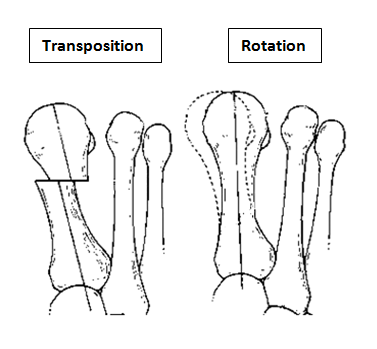

The aim of the surgery is to realign the first metatarsal almost parallel to the second metatarsal. This will move the big toe back into a straight position. This is achieved by cutting the bone. Sometimes re-balancing the soft tissue around the joint or taking a small wedge of bone out of the big toe is also required (Akin). The outcome of your operation will be dependent on the quality of your joint, the degree of arthritis present. There are numerous operations to correct bunions, but essentially, they fall into two categories: transposition and rotational procedures. Transposition osteotomies include the ‘Scarf’ and the ‘capital’. Rotational procedures include the ‘Lapidus’.

A transposition osteotomy such as a Scarf or capital osteotomy is where the bone is cut and moved across. The amount of correction available is restricted by the width of the bone. It is ideally suited to moderate deformities. In severe cases a rotational procedure such as a ‘Lapidus’ is preferred. Here a greater degree of correction is available. This operation also takes longer to heal and to settle down. Either procedure may be combined with an ‘Akin’ to help move the big toe to a straight position.

This is an osteotomy in the metatarsal head (transposition), the metatarsal head is moved to correct the deformity and fixated with a single screw. It is indicated for mild to moderate deformities. The choice to carry out a Scarf or a capital osteotomy will be made by your consultant.

Scarf osteotomy

Lapidus (metatarsal cuneiform fusion)

This involves a fusion of the first metatarsal cuneiform joint, allowing the first metatarsal to be rotated back into a straight position. It is normally reserved for severe deformities. Once the corrected position has been obtained it is usually maintained with a plate and screws.